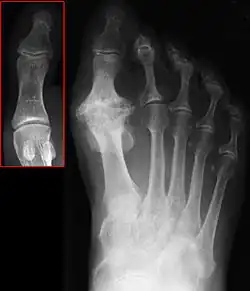

Hallux not labeled but visible at upper left.

Hallux rigidus or stiff big toe is degenerative arthritis and stiffness due to bone spurs that affects the metatarsophalangeal joints (MTP) at the base of the hallux (big toe).